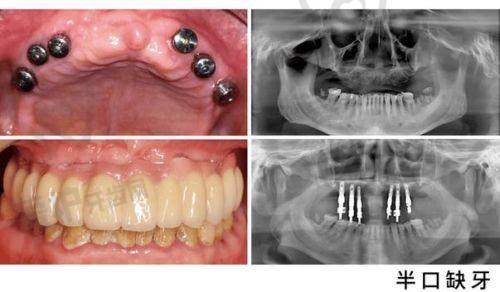

术前检查和评估:患者到西安双宝口腔就诊后,于洪海医生会首先对患者进行全方面的口腔检查,包括口腔X光片、CT扫描等,了解患者的牙槽骨情况、牙齿缺失情况以及全身健康状况。根据检查结果,医生会评估患者是否适合进行半口牙种植手术,并制定个性化的种植方案。

种植体植入手术:在局部麻醉下,医生会在患者的牙槽骨内植入种植体。这个过程需要医生具备不错的技术和丰富的经验,以确保种植体的正确植入。手术时间一般根据种植体的数量和患者的具体情况而定,通常在1-2小时左右。术后患者需要遵循医生的嘱咐,注意休息和口腔卫生,避免感染。

愈合期:种植体植入后,需要一段时间让种植体与牙槽骨形成骨结合。这个过程一般需要3-6个月,具体时间因人而异。在愈合期间,患者需要定期到医院进行复查,观察种植体的愈合情况。

牙冠修复:当种植体与牙槽骨完全结合后,医生会为患者制作并安装牙冠。牙冠的制作需要根据患者的口腔情况和美观需求进行个性化设计,以确保牙冠的舒适度和美观度。安装牙冠后,患者就可以正常使用牙齿进行咀嚼和发音了。